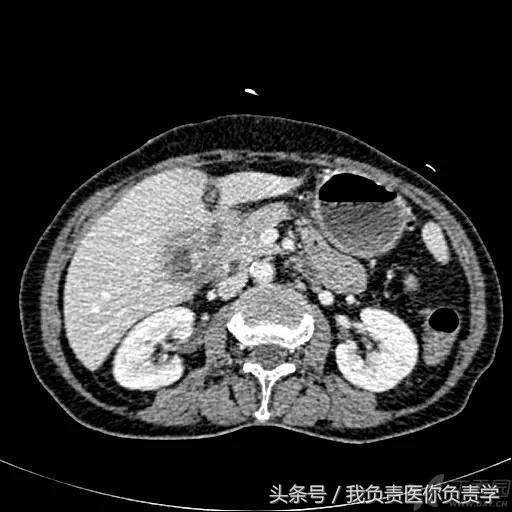

典型病例 5

(由丁香园注册用户「ouchen2010」提供)

患者女,75岁,右上腹疼痛就诊。查体示右上腹压痛明显,无明显腹膜炎体征。

超声检查发现胆囊内可见沉积物及结石回声,胆囊近底部可见 0.5cm 回声中断,十二指肠亦可见 0.5cm 回声中断,二者间见 5.8×4.4cm 混合性团块。

图1示胆囊饱满,内透声差,可见沉积物回声

图2示胆囊、胃窦及十二指肠之间可见混合回声型团块

图3-图5为胆囊局部放大图像,显示胆囊囊壁局部回声中断,周围可见不规则混合回声团块

图6和7为相应CT表现

术后诊断为慢性结石性胆囊炎,胆囊-十二指肠穿孔并内瘘形成。